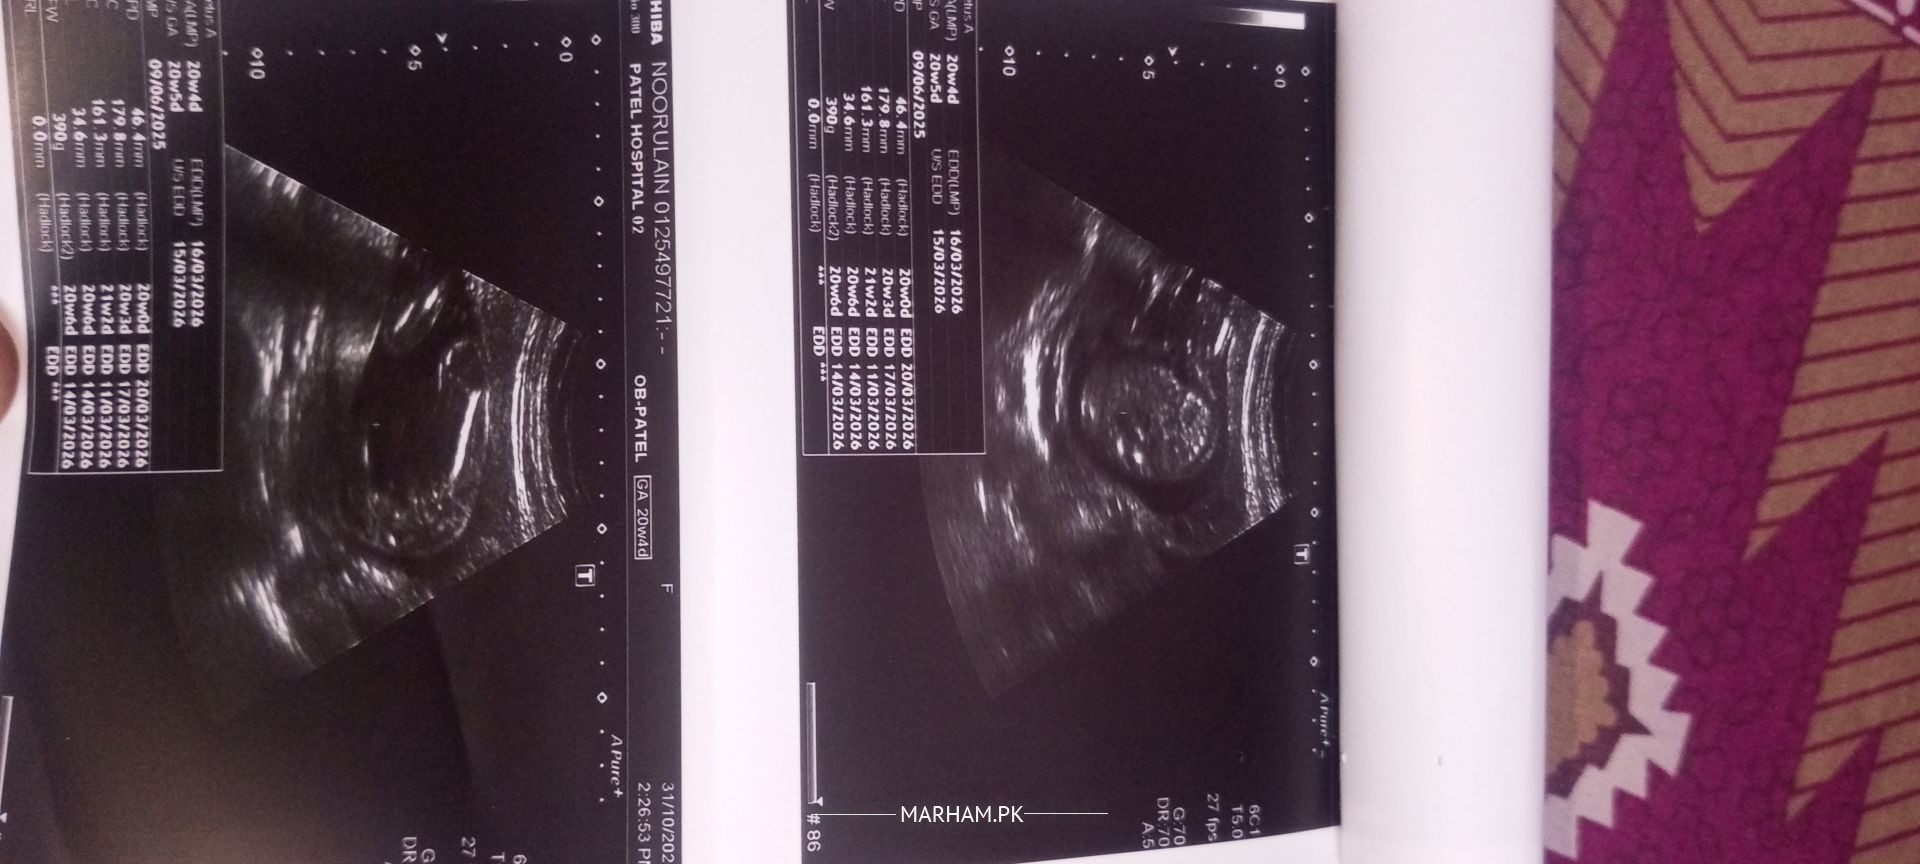

Attached in the anomaly scan report, I would request gynecologists to please comment Could I know baby's gender?

Salam Alaikum overall anomaly scan is normal but there is accumulation of urine in kidneys of fetus ,concern you gynaecologist need proper follow up.

It can resolve later in pregnancy you need serial ultrasound monitoring for this condition .